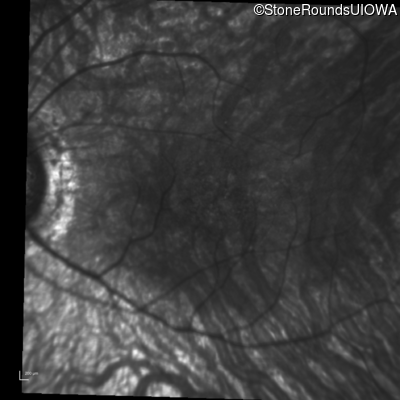

Infrared Fundus Photograph - Right - 20/40

Exemplar